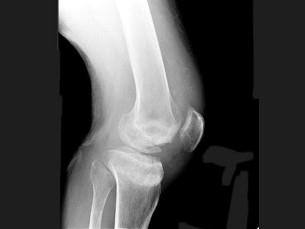

问题 男,67岁,脊髓痨患者,右下肢麻木,右膝关节肿胀,结合图像,最可能的诊断是?(?)

选项 A.创伤性关节炎 B.退行性骨关节病 C.神经性关节病 D.风湿性关节炎 E.痛风

答案 C